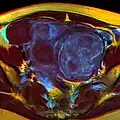

Multiple uterine leiomyoma

Sub-serosal uterine fibroid

Multiple uterine leiomyoma with calcification

Fibroids are monoclonal tumors and approximately 40–50% show karyotypically detectable chromosomal abnormalities. When multiple fibroids are present they frequently have unrelated genetic defects. Specific mutations of the MED12 protein have been noted in 70 percent of fibroids.[30]